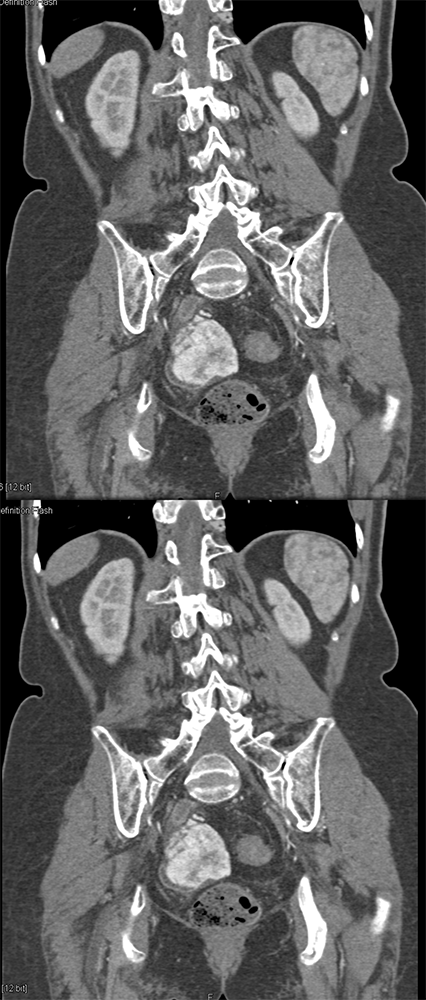

GIST Tumor Duodenum ![]() |

GI Bleed ![]() |

![]() |

“All patterns of enhancement on contrast enhanced computed tomography (CECT) can be seen with GISTs, including hypoenhancing, isoenhancing, and hyperenhancing tumors. They can be large or small, endoluminal or exophytic. Clinical presentations include asymptomatic patients, nonspecific symptoms, obstruction, and bleeding. Bleeding can take the form of slow, intraluminal GI bleeding or massive intraperitoneal bleeding secondary to rupture and can be seen regardless of the enhancement pattern.” Getting the GIST: a pictorial review of the various patterns of presentation of gastrointestinal stromal tumors on imaging. Scola D et al. Abdom Radiol 2017 May;42(5):1350-1364. |

“Occasionally, patients may present with GI bleeding, which may be occult or take the form of frank hemorrhage with hemodynamic instability. Likewise, tumors can rupture on the external surface, causing intraperitoneal hemorrhage which can be life threatening.” Getting the GIST: a pictorial review of the various patterns of presentation of gastrointestinal stromal tumors on imaging. Scola D et al. Abdom Radiol 2017 My;42(5):1350-1364. |